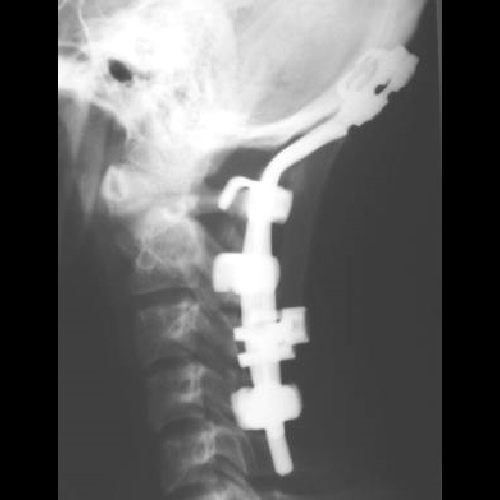

Титановая конструкция для окципитоспондилодеза Тип 1

Конструкция состоит из шейных ламинарных крючков, затылочных крючков, затылочно-шейного стержня, блокирующих гаек и поперечной стяжки (коннектор).

Для задней фиксации верхнешейного отдела позвоночника при его тяжелых повреждениях и заболеваниях.